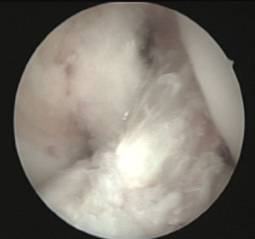

En aquellos pacientes inmaduros con inestabilidad anterior de la rodilla sintomática utilizamos la reconstrucción artroscópica transepifisaria con tendón semitendinoso del paciente.

Se evita el daño del cartílago de crecimiento mediante el empleo de tunelizaciones retrógradas (sistema de retroconstrucción) que nos permite restituir la funcionalidad de la articulación sin afectar el cartílago de cremiento y manteniendo la isometría del injerto implantado.

Existe asimismo la posibilidad de lesiones parciales del ligamento cruzado en las que sólo se encuentre afecto uno de los fascículos del mismo (antero medial o póstero lateral).

Cuando su afectación determina la presencia de sintomatología clínica se aconseja la reparación selectiva del fascículo lesionado mediante ligamentoplastias de refuerzo artroscópicas preservando los restos de ligamento cruzado anterior funcionantes.